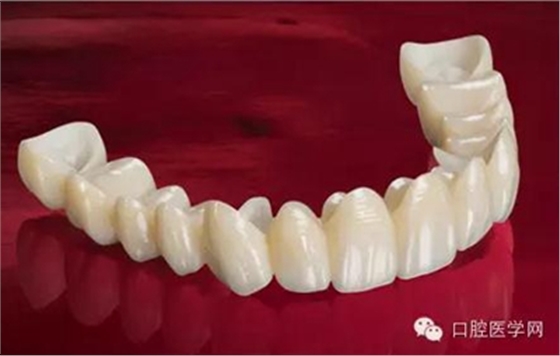

做完根管治療以后的牙齒,強(qiáng)度是有下降的,因?yàn)橹暗凝x壞,以及我們治療時為了讓器械能夠順利的進(jìn)入根管內(nèi)部,要磨除一些牙體組織。為了防止牙齒因?yàn)樽陨韽?qiáng)度下降而折斷,我們要給這個牙做一個全冠修復(fù),有時候在做冠之前還要在根管里放一個樁進(jìn)行加固。